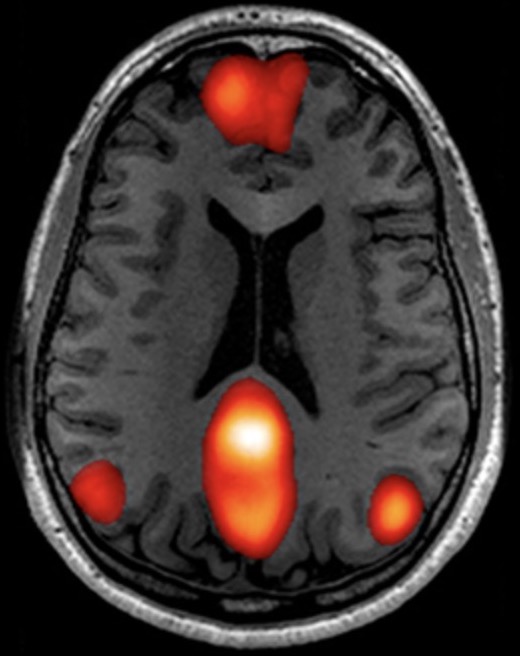

• 功能磁共振(fMRI)数据处理业务

功能磁共振(fMRI)数据处理业务

主要包括:

1. 数据质量检查;2. 数据预处理;3. 静息态功能磁共振(rs-fMRI)指标分析;4. 任务态功能磁共振(task-fMRI)数据分析;5. 独立成分分析;6. 脑网络与大脑动态特性分析;7. 脑影像机器学习分析;8. 客户定制化分析服务等。